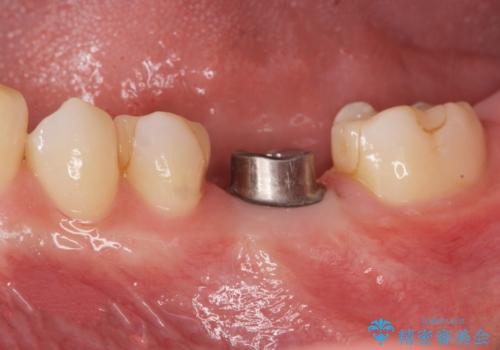

欠損部のインプラント補綴

- 失った奥歯にインプラント治療を受けたい、と希望され来院されました。

前後の歯を削らずに機能回復できるインプラントを用いて審美生、咬合機能の回復を計画します。

痛みや腫れもほとんどなくインプラント治療を終えられ、しっかり噛むことができるようになった。と治療結果に満足いただくことができました。